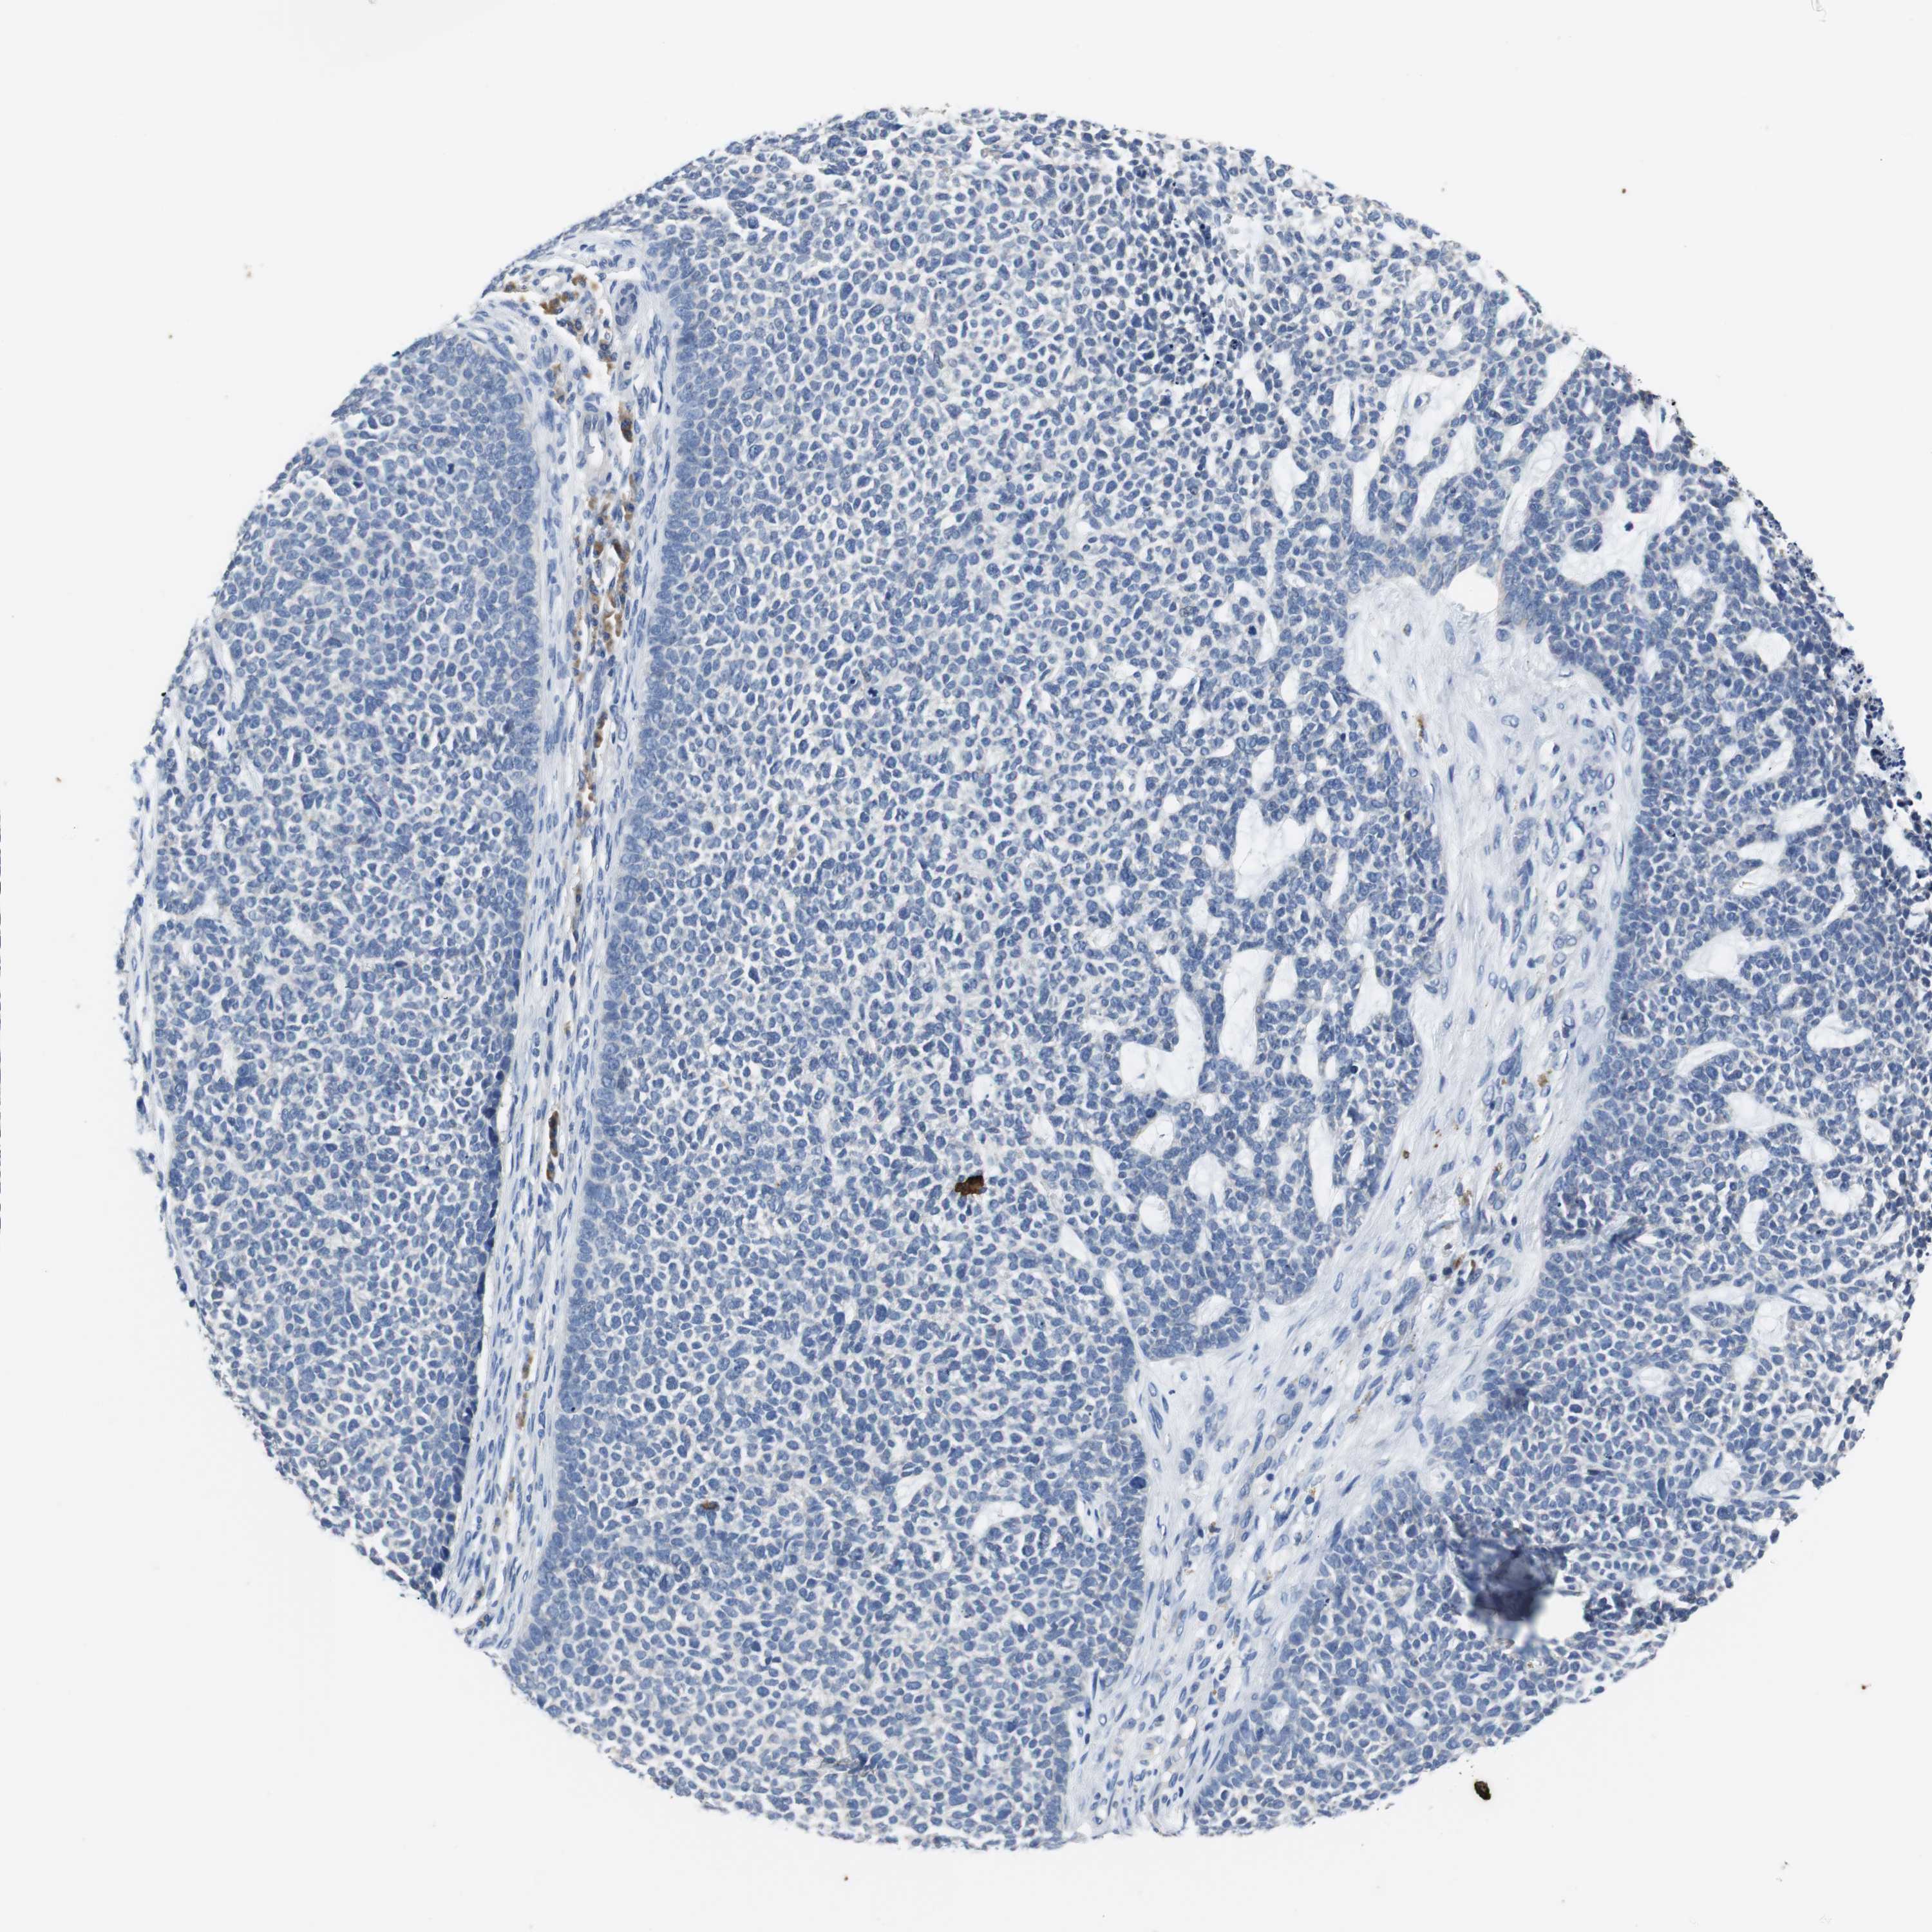

SKIN CANCER - Protein expressioni

A mouse-over function shows sample information and annotation data. Click on an image to view it in a full screen mode. Samples can be filtered based on level of antibody staining by selecting one or several of the following categories: high, medium, low and not detected. The assay and annotation is described here.

Each image is clickable and will lead to virtual microscopy that enables deeper exploration of all samples and also displays staining intensity scores, fraction scores and subcellular localization as well as patient and tissue information for each sample.

Antibody HPA006277

Antibody HPA006507

Antibody CAB017027

Staining

High

Medium

Low

Not detected

Intensity

Strong

Moderate

Weak

Negative

Quantity

>75%

75%-25%

<25%

None

Location

Nuclear

Cytoplasmic/membranous

Cytoplasmic/membranous,nuclear

Squamous cell carcinoma, NOS

Basal cell carcinoma

Squamous cell carcinoma, metastatic, NOS